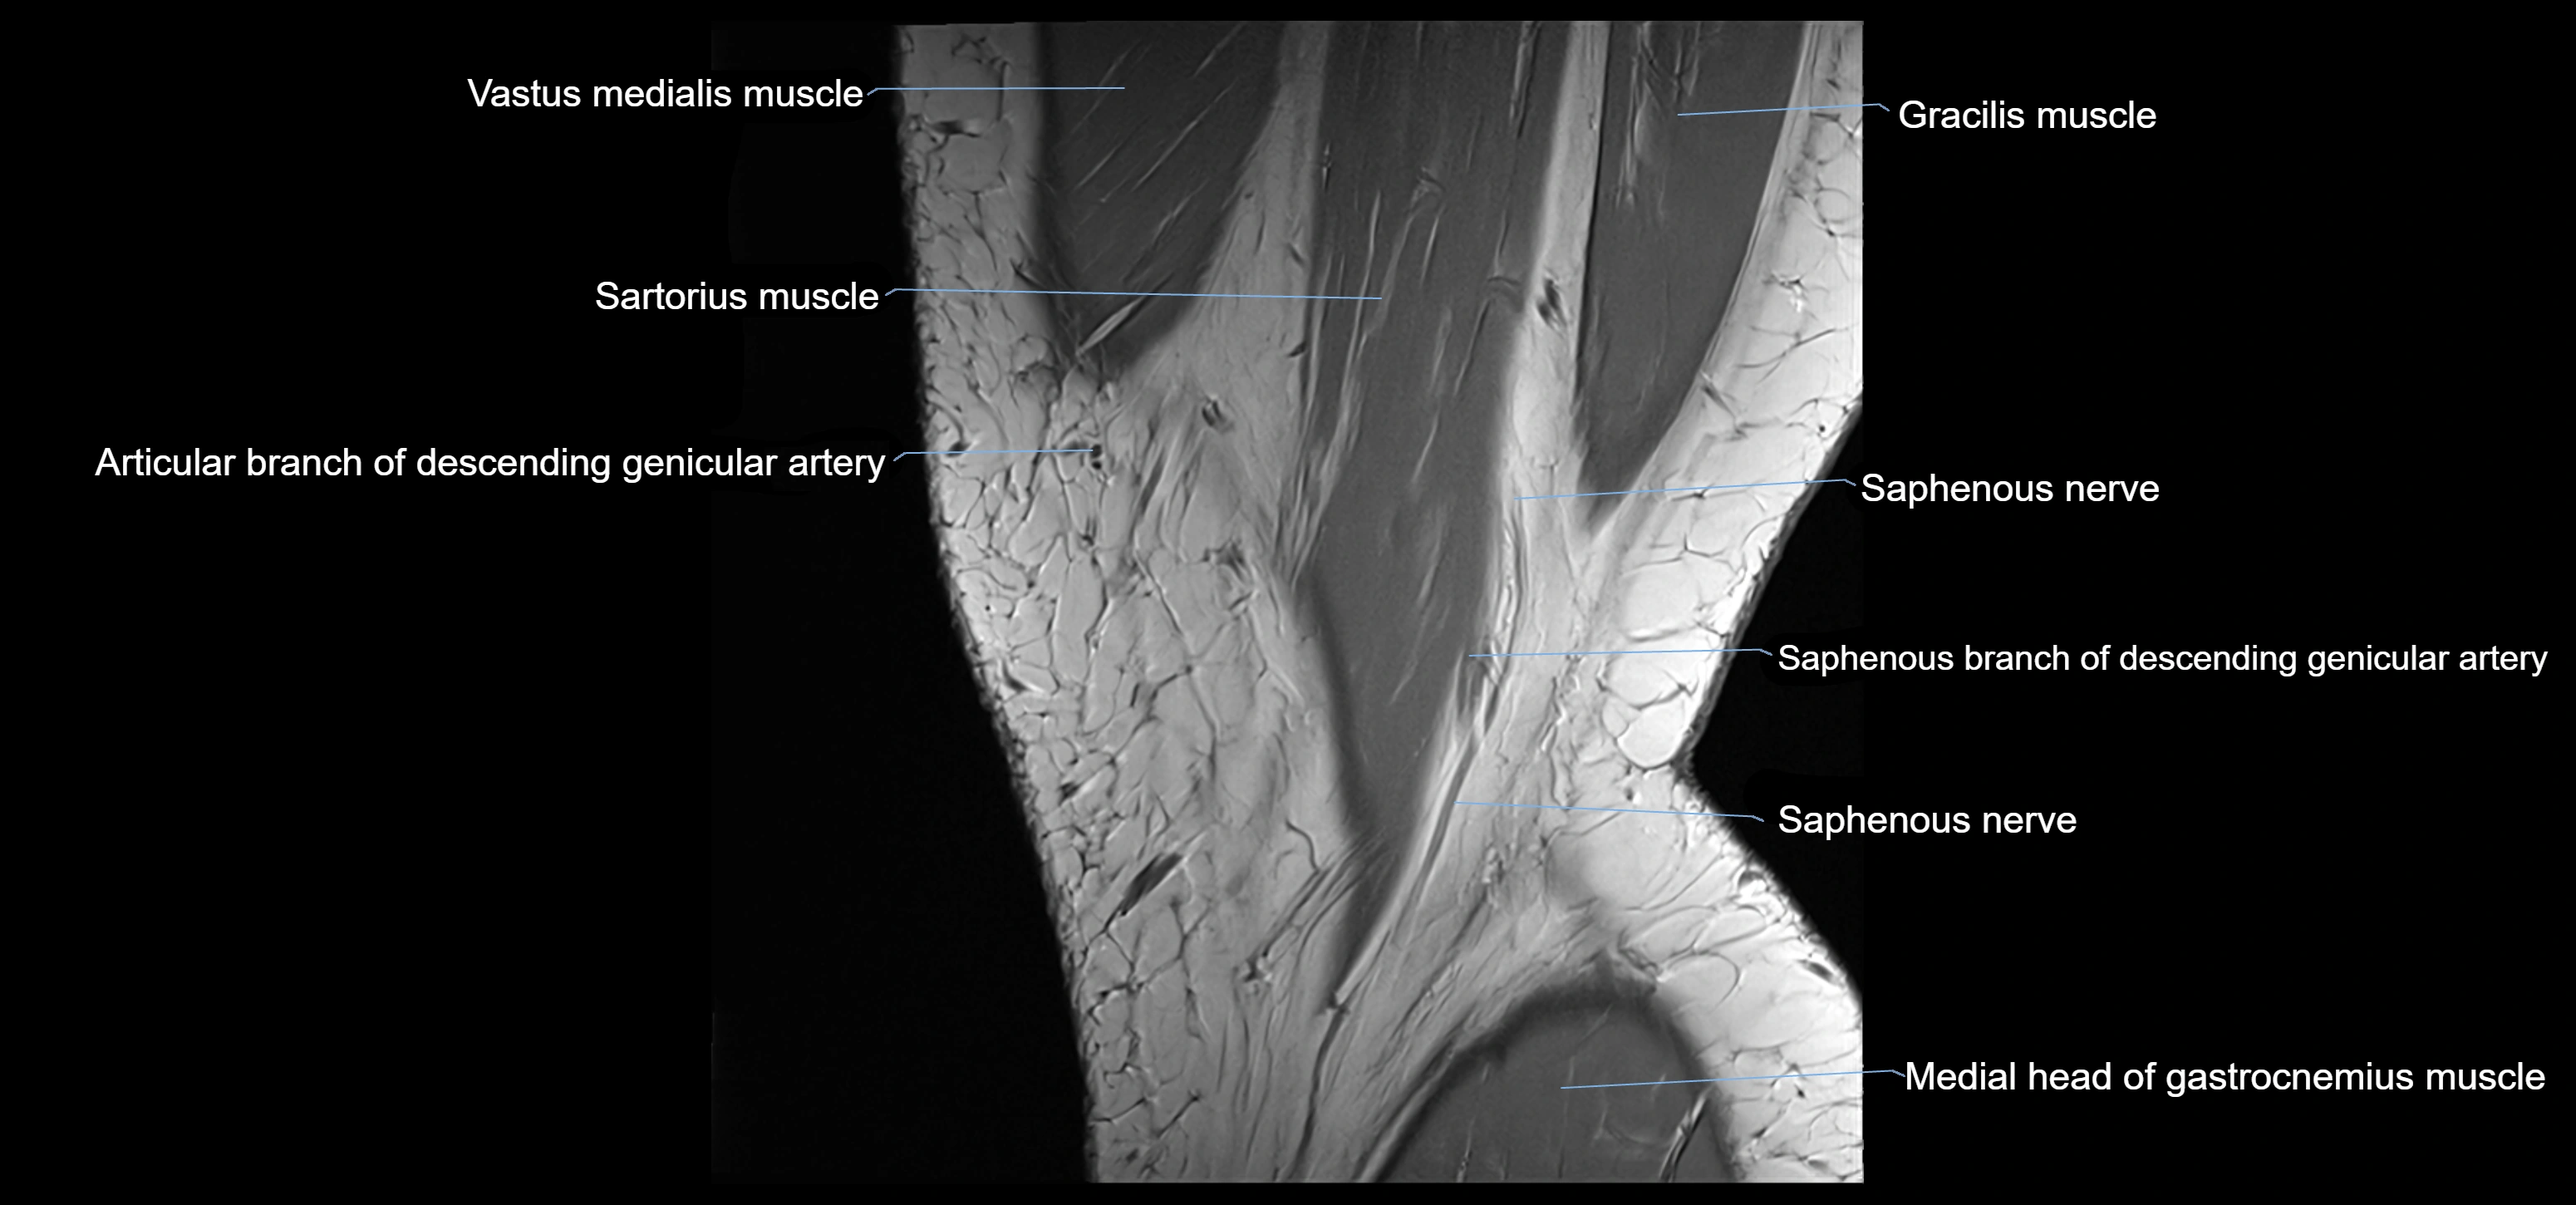

- Saphenous nerve

- Sartorius muscle

- Descending genicular artery (Saphenous branch)

- Descending genicular artery (Articular branches)

- Medial head of gastrocnemius muscle

- Gracilis tendon (Distal)